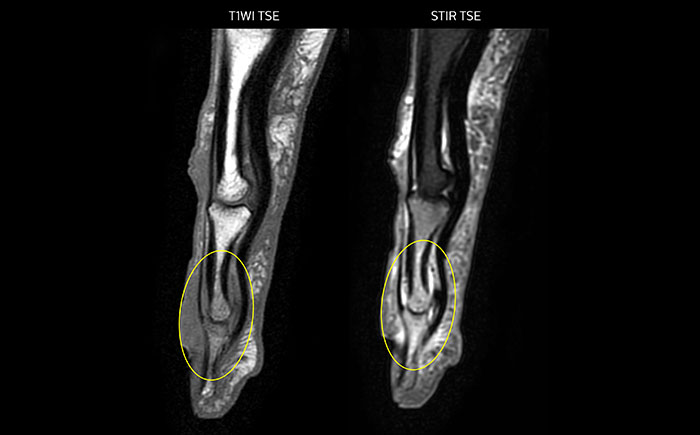

MR-Untersuchung mit Prodiva 1.5T, 72-jährige Patientin mit malignem Melanom am Knöchel. mDIXON TSE bietet eine hervorragende Fettsuppression ohne Verzerrung, wie sie ansonsten bei diesen Extremitäten häufig auftritt.

Scandauer: 2:55 Minuten, FOV: 160 mm, erfasste Voxel: 0,55 x 0,83 x 3,0 mm.

Scandauer: 04:19 Minuten, FOV: 160 mm, erfasste Voxel: 0,55 x 0,80 x 3,0 mm.

Scandauer: 02:50 Minuten, FOV: 160 mm, erfasste Voxel: 0,70 x 0,99 x 3,0 mm.